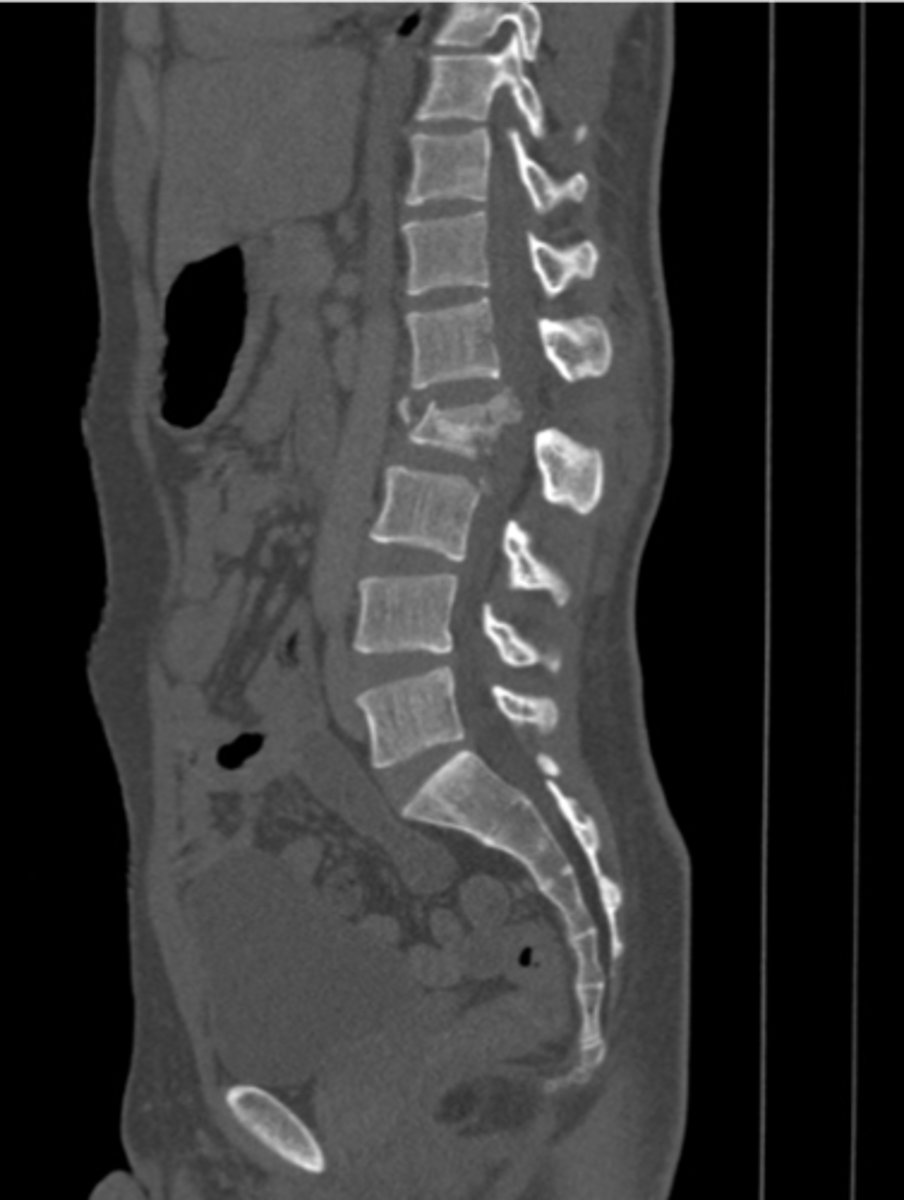

CT myelography can be used to evaluate the ____ and _____

spinal cord and canal

CT myelography is a good alternative to MRI to identify

spinal stenosis, disc herniation, spondylosis, arthritis

spinal stenosis

Narrowing of the spinal canal that causes pressure on the spinal cord (nerves)

spinal stenosis etiology

osteophytes, disc herniation, tumors, trauma